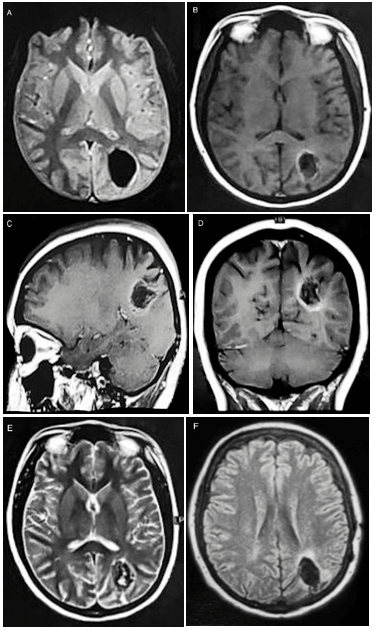

Figure 2: A) Preoperative brain MR showing a predominantly hypointense signal parietal lesion suggestive of calcification on T2*; B-D) A high intensity peripheral signal, that can be seen also in cavernomas and other hemorrhagic lesions, on unenhanced and post contrast T1-weighted images; E) An heterogeneous signal intensity on T2-weighted image; and F) A small amount of perilesional edema on FLAIR.

The electroencephalogram disclosed left centrotemporal cortical epileptogenic activity. Head computed tomography (CT) showed a nodular calcified lesion, located in the left precuneus and inferior parietal lobule (Figure 1). On brain magnetic resonance (MR), there was an oval-shaped lesion measuring 2.7 x 2.4 x 1.9 cm in its largest axes, of heterogeneous intensity but with a low signal intensity predominance, mainly on the susceptibility-weighted sequences, without restricted diffusion or contrast enhancement (Figure 2). There was little adjacent edema. Considering the significance of the voluminous calcification, a screening for metabolic disturbances of some minerals was performed: calcium, magnesium, ferritin, T4 (thyroxine), TSH (thyrotrophic stimulating hormone), calcitonin, and parathormone serum levels were normal, while phosphorus and transferrin serum levels were below the normal range. Cervical ultrasound depicted a well-defined solid oval nodule, predominantly hypoechogenic, located in the left thyroidal lobe, with central and peripheral vascularization; the parathyroid regions, though, did not show any abnormalities. At this moment, the diagnostic hypotheses of cavernoma, calcified neurocysticercosis, and calcified intra-axial meningioma were proposed. A lumbar tap was then performed, and the cerebrospinal fluid analysis was completely normal, being the immunological test (ELISA) for neurocysticercosis negative.